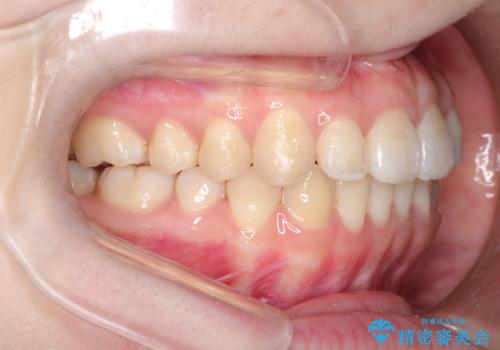

前歯がガタガタ・噛み切りにくい インビザラインによる歯を抜かない矯正

前歯にがたつきがあり、上下の歯が咬み合っていない状態でした。

歯列の横幅をひろげるのと、歯と歯の間をわずかに削ることにより、前歯のがたつきと、開咬を改善しました。